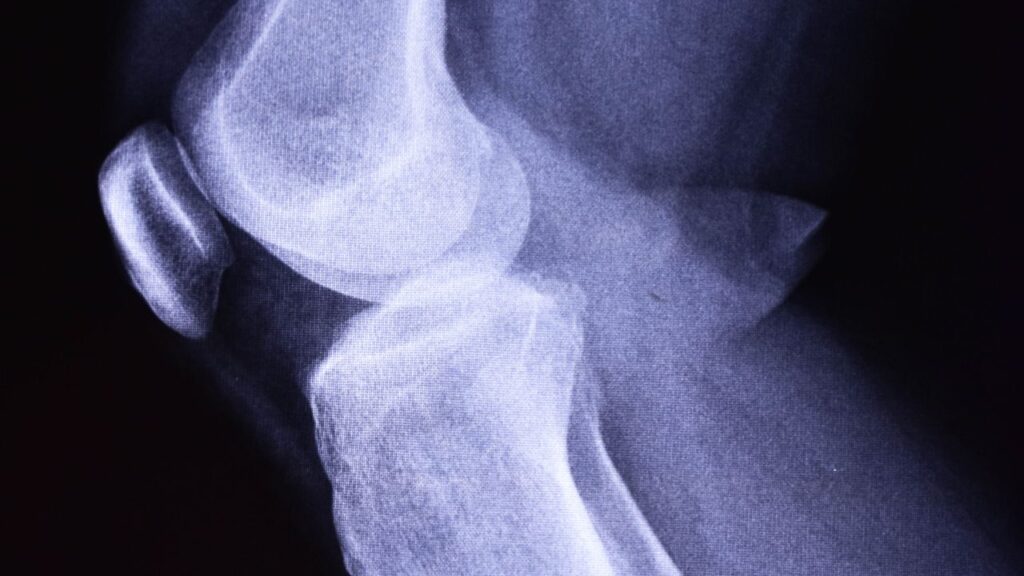

Para entender bem a condição, vamos começar traduzindo o CID. A gonartrose, identificada pelo CID M17, é o que chamamos popularmente de artrose ou “desgaste” no joelho. Imagine a articulação do seu joelho com as duas peças que se encaixam.

Entre elas, existe uma camada de cartilagem, que é lisa e macia, como uma almofada, permitindo que o movimento seja suave e sem dor.

A gonartrose acontece quando essa “almofada” de cartilagem se desgasta. Sem essa proteção, os ossos começam a raspar um no outro. É esse atrito que causa a dor, o inchaço, os estalos e a sensação de que o joelho está “arranhando” ou “travando”.